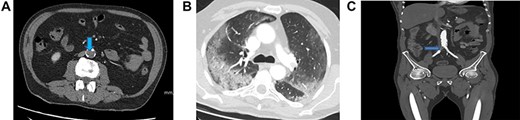

Blood investigations showed an elevated white blood cell count (WCC), a low lymphocyte count and elevated C-reactive protein (CRP). The thrombin time was prolonged (Table 1). A computed tomography (CT)—angiogram of lower limbs showed complete thrombosis of the infrarenal aorta, the common and external iliac arteries bilaterally, the left common, proximal superficial and profunda femoral arteries (Fig. 1A). A CT scan of the chest showed patchy and ground-glass shadowing predominantly in the bilateral lower lung lobes (Fig. 1B). A throat swab was positive for COVID-19.

(A) A CT scan of the chest showed patchy and ground-glass shadowing predominantly in the bilateral lower lung lobes. (B) CT-thorax showing pulmonary changes. (C) CT-angiogram demonstrating aorta and left CIA patency with residual thrombus in right CIA post-operatively (blue arrow)

A repeat CT-angiogram was performed. It confirmed that much of thrombus within the distal aorta and left common iliac arteries had been successfully removed; there was still a 25 mm occlusion in the proximal segment of the right common iliac artery with distal flow (Fig. 1C).